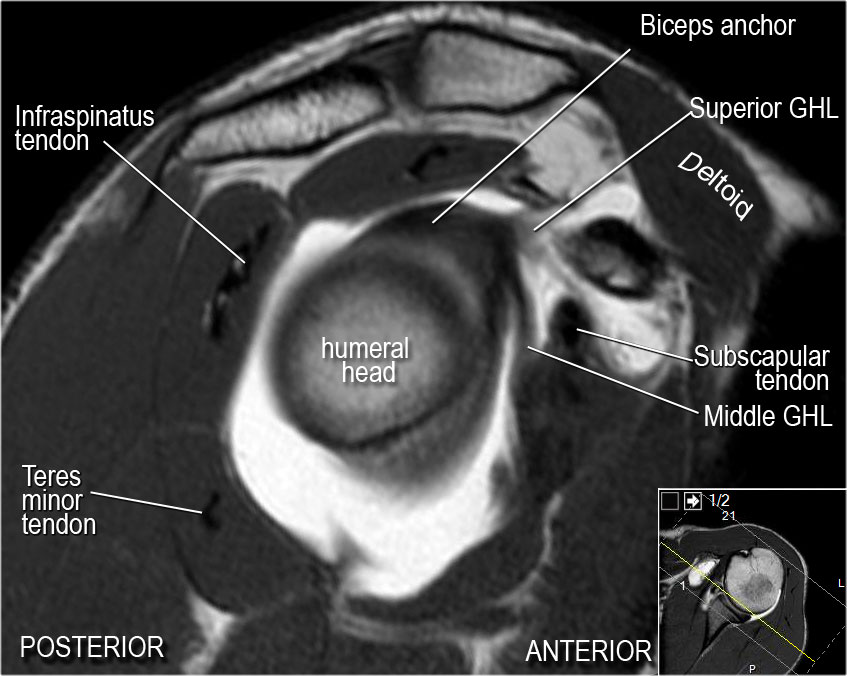

How to locate glenohumeral ligaments.

1-Axial views